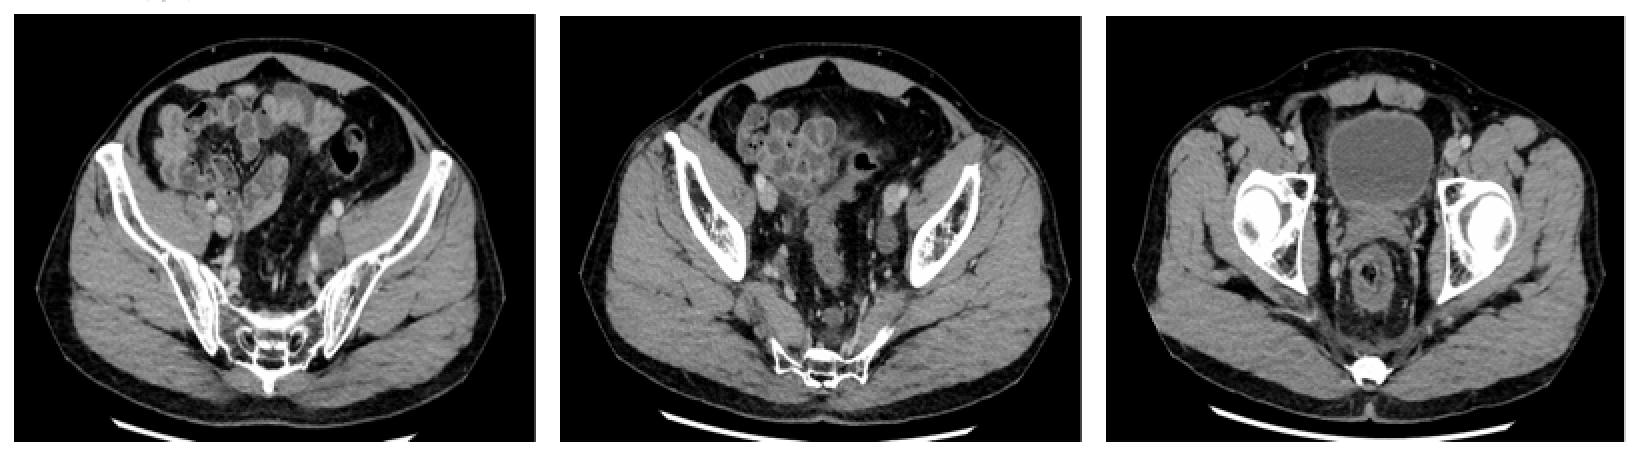

全腹CT

直肠中下段肠壁增厚,考虑直肠癌,伴直肠周围间隙、直肠旁间隙、双侧髂血管旁淋巴结增多、增大,请结合临床及其他检查。

左侧肾上腺结节,转移?腺瘤?或其他?左肾前下份轮廓欠光整,慢性炎症改变?左肾小囊肿。

肝右后叶上段钙化灶

直肠中下段肠壁增厚,考虑直肠癌,伴直肠周围间隙、直肠旁间隙、双侧髂血管旁淋巴结增多、增大,与2016-12-2日旧片比较,左侧髂血管旁淋巴结略缩小,其余未见明显变化,请结合临床及其他检查。

左侧肾上腺结节,转移?腺瘤?或其他?与上述旧片比较未见明显变化。

左肾前下份轮廓欠光整,慢性炎症改变?左肾小囊肿。

肝右后叶上段钙化灶。

前列腺钙化灶。

直肠中下段肠壁增厚,考虑直肠癌,伴直肠周围间隙、直肠旁间隙、双侧髂血管旁淋巴结增多、增大,与2017-02-14日旧片比较,直肠壁增厚较前减轻,其余未见明显变化,请结合临床及其他检查。

腹部CT

“直肠癌术后”,未见明显复发征象,请结合临床及其他检查。

腹盆腔少许积液,盆底筋膜增厚。双侧盆壁内侧斑片状及片状不规则低密度影,未见明显强化,积液可能,请随访。

左侧肾上腺结节,转移?腺瘤?或其他?与2017-04-26旧片比较未见明显变化。

左肾前下份轮廓欠光整,慢性炎症改变?

左肾小囊肿。